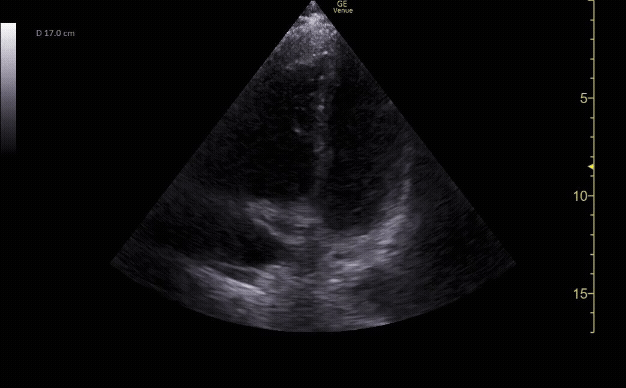

Subxiphoid view showing the liver, right ventricle, right atrium, left atrium, and left ventricle.

c/o Kyle Ackerman, MD